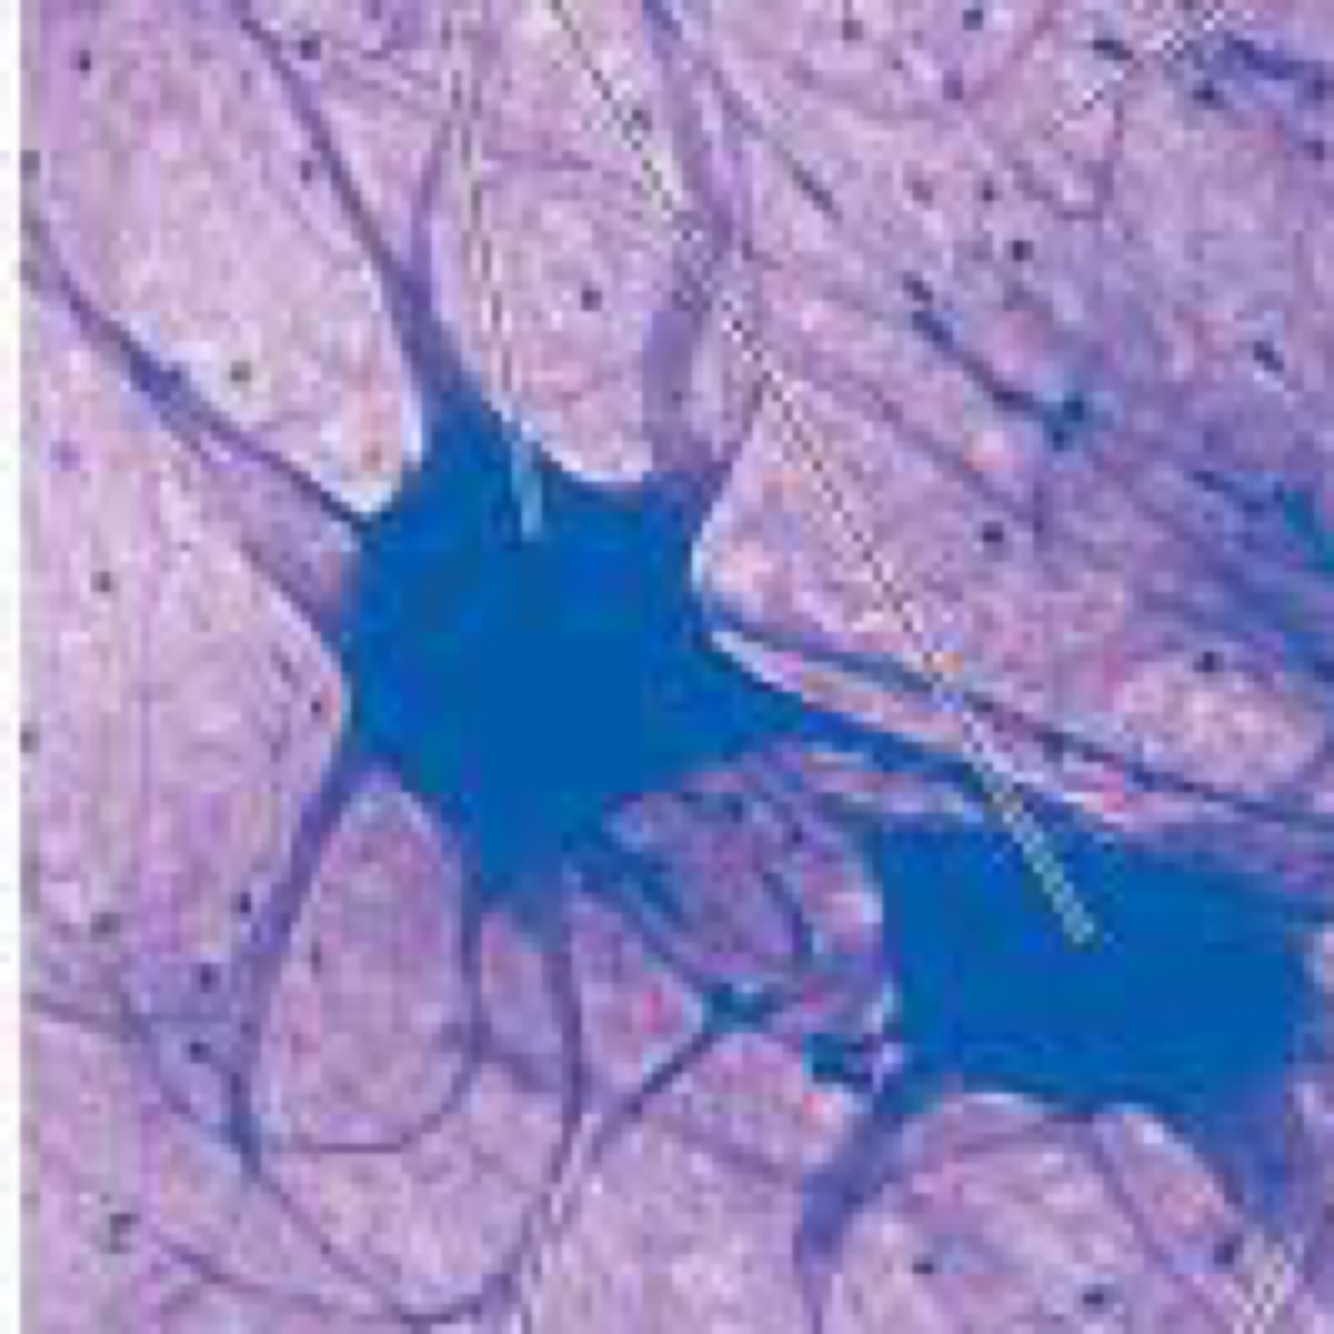

Q

ID the tissue

A

Nervous tissue

ID the cell type by the pointer . What are 3 functions of this cell?

Neuron. Receive, process, and transmit information (action potential)